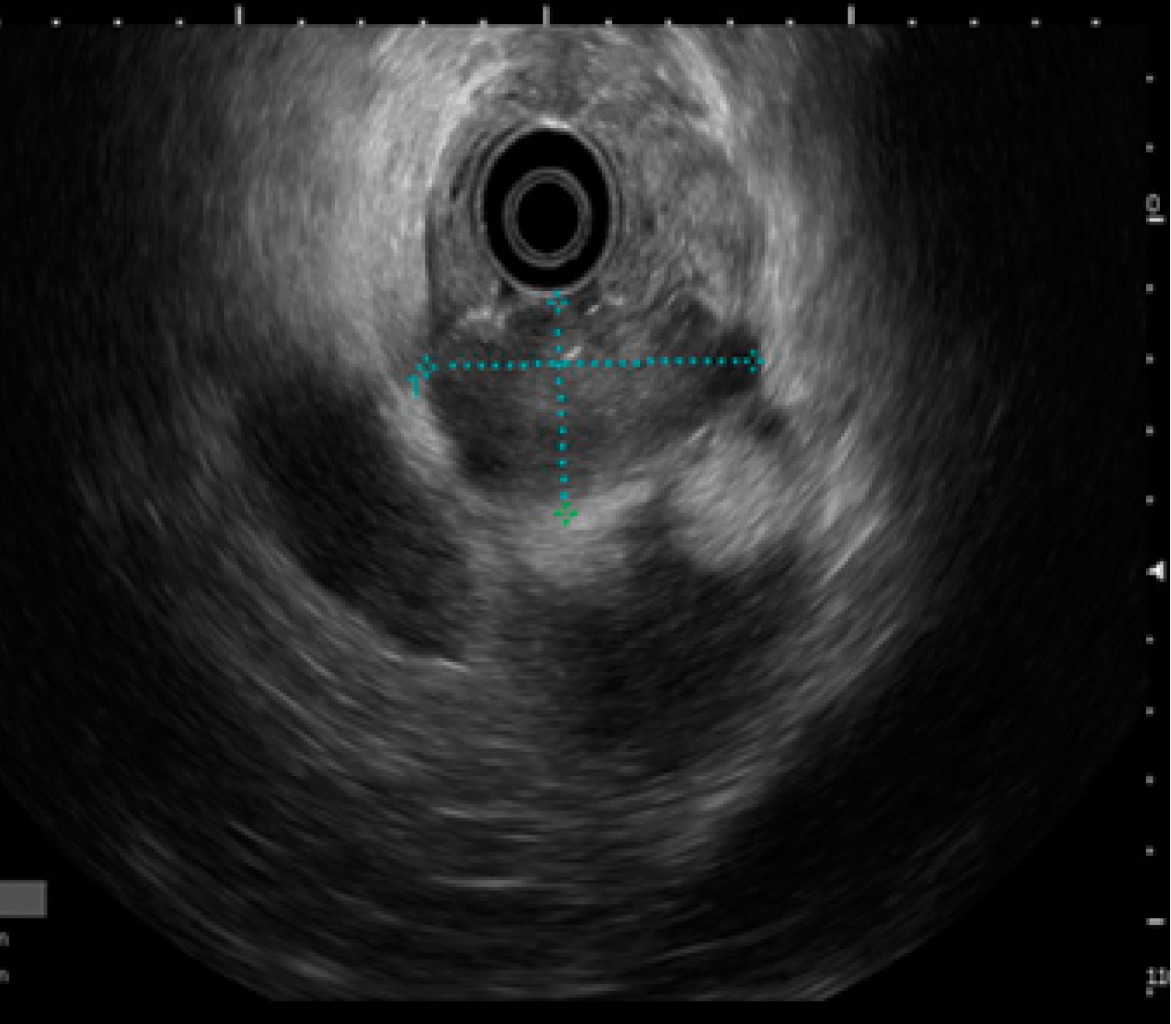

Introducción: La prevalencia de cáncer gástrico en México ha tenido un incremento en los últimos años con predominio en hombres. Los factores de riesgo son el consumo de alcohol, tabaco e infección por Helicobacter pylori, considerado en nuestra población como de riesgo moderado. Aunque el adenocarcinoma sigue predominando como la neoplasia maligna gástrica más frecuente, un porcentaje no despreciable del 7-8%, según la Organización Mundial de la Salud, lo ocupa el linfoma no Hodgkin (extranodal) y los leiomiosarcomas. El adecuado abordaje diagnóstico y la diferenciación son cruciales entre el adenocarcinoma y el linfoma, ya que de ello depende el pronóstico y el tratamiento. Caso clínico: Se comunica el caso de un hombre de 79 años con astenia, hipercalcemia maligna con hallazgo incidental de engrosamiento gástrico por tomografía. Se realizó ultrasonido endoscópico para el diagnóstico de linfoma gástrico de variedad difuso (Ann Arbor modificada II2). Revisión de literatura: El ultrasonido endoscópico es considerado una herramienta para el diagnóstico de neoplasias malignas gástricas en todas sus variantes, principalmente donde la enfermedad se encuentra en capas profundas. Conclusión: El ultrasonido endoscópico es el método que nos lleva a obtener alta precisión diagnóstica en linfoma gástrico permitiendo la toma de biopsias del espesor total de la pared de bloque celular para realizar diagnóstico diferencial siempre con inmunohistoquímica.

Figura 3